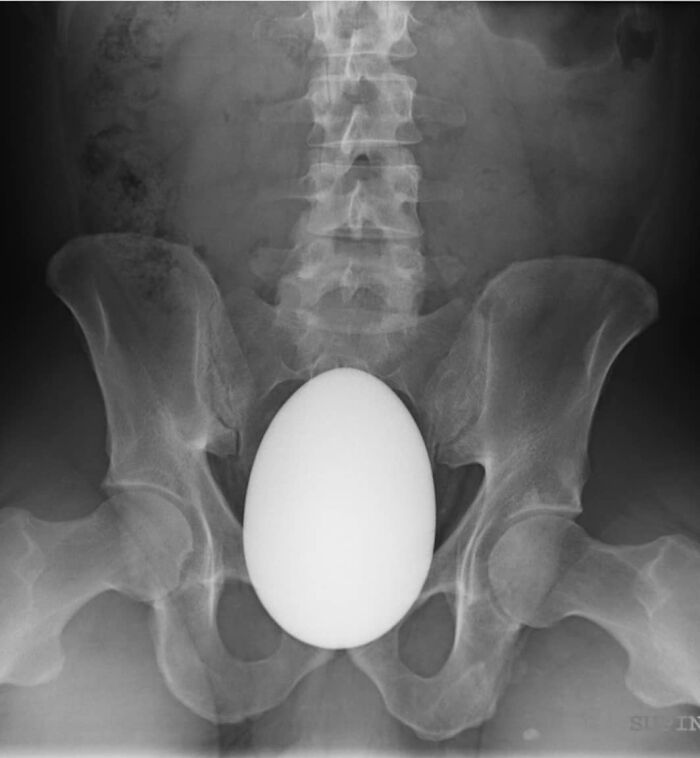

#75 A Patient Had Inserted In His Rectum Approximately 2 H Prior To Presentation

Image credits: medicalpedia